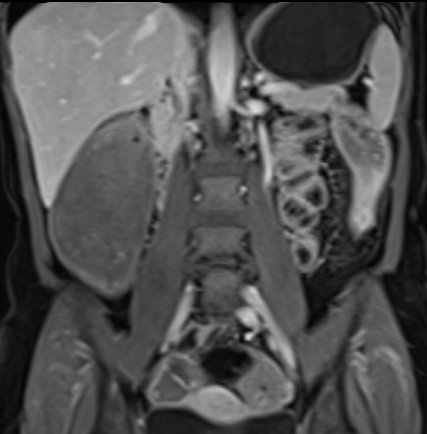

Bệnh nhân nữ 48 tuổi, đang điều trị bằng thuốc kháng TNF, được chỉ định nội soi đại tràng.

Phát hiện hẹp lòng ruột ở đại tràng sigma, không thể vượt qua được khi nội soi.

MR-enterography được thực hiện để đánh giá mức độ lan rộng của chỗ hẹp.

Ruột non bình thường, nhưng ghi nhận các đoạn hẹp ở đại tràng xuống và đại tràng ngang.

Cả hai đoạn hẹp đều có thành ruột dày đến 8 mm và ngấm thuốc rõ rệt theo kiểu niêm mạc ở đại tràng xuống và kiểu phân lớp ở đại tràng ngang.

Giãn ruột trước chỗ hẹp được ghi nhận ở cả hai đoạn.

Do các chỗ hẹp này không hiện diện khi nội soi đại tràng trước khi điều trị kháng TNF, nhiều khả năng chúng đã hình thành trong quá trình điều trị.

Do đó, quyết định phẫu thuật cắt đại tràng gần toàn bộ với miệng nối hồi-sigma đã được đưa ra.